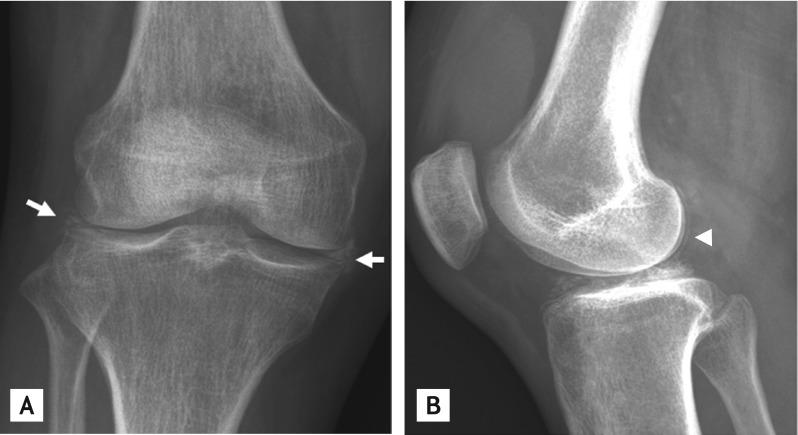

Figure 2

Dual energy computed tomography shows multiple calcium depositions in (A) both menisci, femoral condylar cartilage (arrowheads) and posterior cruciate ligament (arrow) and (B) anterior cruciate ligament (arrow).

A 52-year-old woman presented with painful swelling in both knees for 7 days. Physical examination identified marked swelling and tenderness in both knee joints that she reported to have recurred for the past 6 years. Laboratory tests determined the erythrocyte sedimentation rate to be 107 mm/hr, C-reactive protein as 25.55 mg/dL, and serum uric acid levels as 4.1 mg/dL. Calcium pyrophosphate dihydrate (CPPD) crystals were found on polarized light microscopy examination of knee joint synovial fluid. Cultures identified no microorganisms. Plain radiography of the right knee revealed multiple calcifications in the medial and lateral menisci and the femoral condylar cartilage (Fig. 1). Dual-energy computed tomography (DECT), which differentiates monosodium urate (color-coded in green) from calcium (color-coded in blue), revealed multiple calcium depositions in the anterior and posterior cruciate ligaments, as well as in both menisci and the femoral condylar cartilage (Fig. 2). The patient was diagnosed as having CPPD crystal deposition disease of both knee joints. Intra-articular injection of triamcinolone effectively relieved her pain.

In gouty arthritis, DECT is a useful noninvasive and inexpensive imaging modality for detecting urate deposits, especially when the acquisition of synovial fluid tophi is not possible and both septic arthritis and CPPD crystal deposition disease are possible diagnoses. DECT is also useful for detecting coronary calcium deposition and urinary calculi. Although calcification is often easily recognized on plain radiographs, DECT is a useful tool when crystal examination is not available or radiography is not easily interpretable.